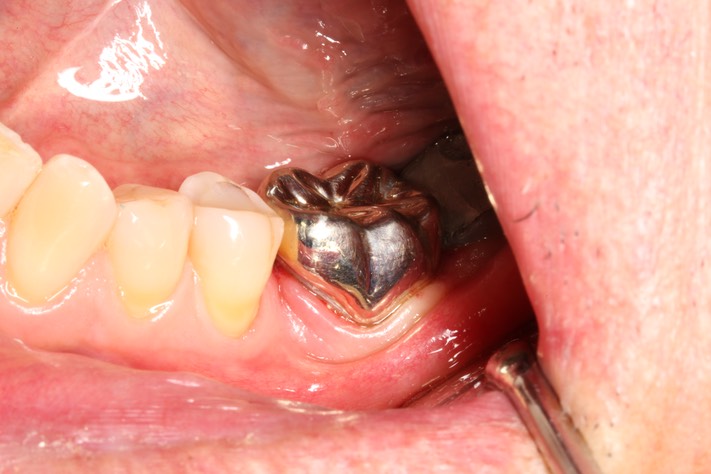

Matt Dodson #18 buccal view